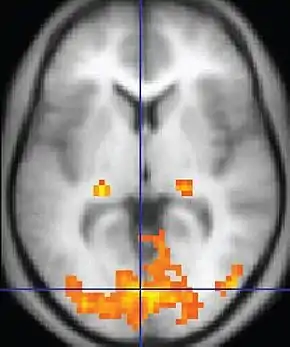

| Functional MRI (fMRI) | Blood-oxygen-level dependent imaging | BOLD | Changes in oxygen saturation-dependent magnetism of hemoglobin reflects tissue activity.[90] | Localizing brain activity from performing an assigned task (e.g. talking, moving fingers) before surgery, also used in research of cognition.[91] |  |